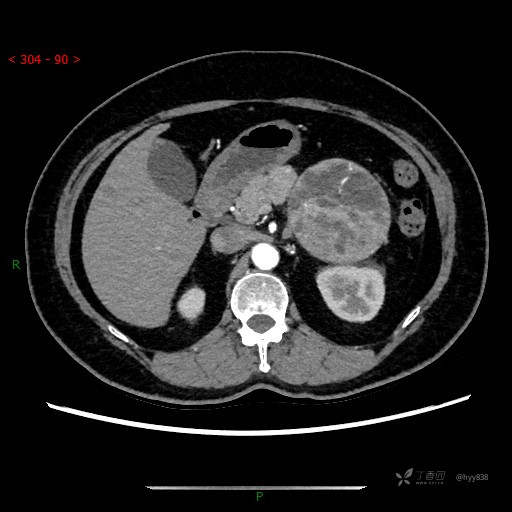

增强静脉期